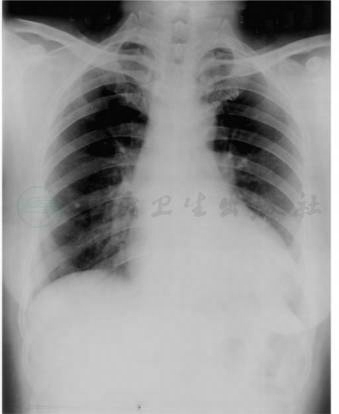

左心室增大和升主动脉呈“主动脉型”,左心室有不同程度的增大。心功能不全时左心房亦可增大,但程度较轻,同时伴有肺静脉高压征象。升主动脉狭窄后扩张是狭窄后扩张是其基本征象,心影不大或轻中度增大,诊断主动脉狭窄的重要依据,但与左心室增大程度、瓣口狭窄程度无明显相关。左心室及心脏明显增大者多为重度主动脉瓣狭窄(图2)。

主动脉瓣钙化是主动脉瓣受损的可靠征象,提示瓣口可能有重度狭窄。透视下,可见左心室及升主动脉搏动增强。

图2主动脉瓣狭窄

心影呈“主动脉型”,主动脉结大,心腰凹陷,左心室增大

引自:实用放射学.第4版.ISBN:978-7-117-28542-1.主编: